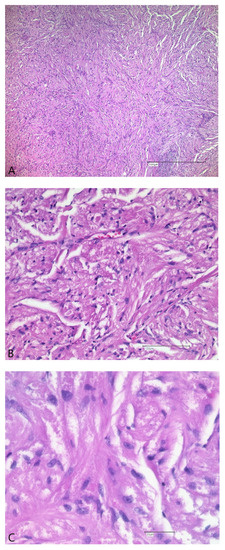

2.2. Surgical Treatment and Outcome